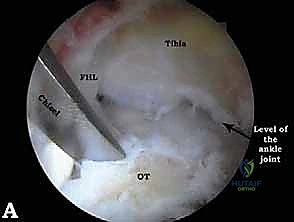

الخطوة 2: إنشاء المداخل الجراحية (Portals)

بدلاً من الشقوق الكبيرة، يقوم الدكتور هطيف بإجراء شقين صغيرين جداً (حوالي 0.5 سم لكل منهما) على جانبي وتر أخيل.

* المدخل الخلفي الجانبي (Posterolateral Portal).

* المدخل الخلفي الداخلي (Posteromedial Portal).

يتم تحديد هذه المداخل بدقة متناهية لتجنب إصابة العصب الربلي (Sural Nerve) والحزمة الوعائية العصبية.

الخطوة 3: الاستكشاف البانورامي (Diagnostic Arthroscopy)

يتم إدخال كاميرا المنظار عالية الدقة (4K) عبر أحد المداخل، بينما تُستخدم الأدوات الجراحية الدقيقة في المدخل الآخر. تتيح الكاميرا للدكتور هطيف رؤية الهياكل الداخلية مكبرة عشرات المرات على شاشة عملاقة، مما يسمح بتقييم دقيق للمفاصل، الأوتار، والأربطة.

* استئصال العظم الزائد (Os Trigonum Excision): يتم فصل العظم الزائد بحذر عن الأنسجة المحيطة واستخراجه بالكامل، مما يزيل سبب الانحشار والألم فوراً.

* تحرير وتنظيف وتر (FHL): إذا كان الوتر ملتهباً ومحاصراً، يتم قطع سقف النفق الليفي لتحريره، وإزالة الأنسجة الملتهبة (Tenosynovectomy) لضمان انزلاقه بحرية.